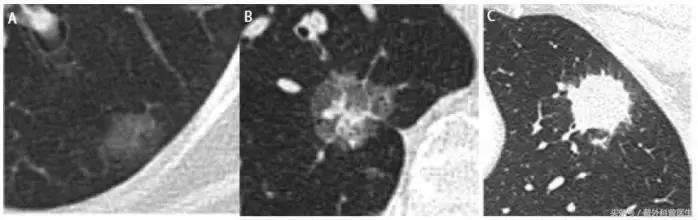

如果这个结节很小,直径在2厘米以下就称作“肺小结节”。根据这个结节实性成分的不同通常分为以下三类:

A. 纯磨玻璃样结节(GGO):这种结节在CT上的表现像磨砂玻璃一样,似透非透,跟周围正常的肺组织对比不是那么明显(图A)。说明它的密度和肺的差不太多。

B. 部分磨玻璃样结节:表现为在磨玻璃的基础上有部分的对比比较明显的实性成分或者空泡成分(图B)。介于A和C之间。

C. 实性结节:与周围肺组织对比很明显的致密均匀的实性阴影(图B)。说明这个“疙瘩”比较实在。